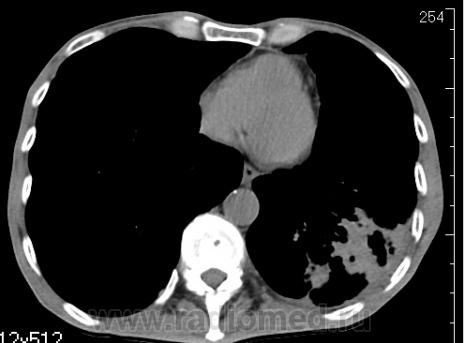

На фоне консолидации полость без содержимого. Может быть всё что угодно, что сопровождается деструкцией. Нужны ещё томограммы в лёгочном окне.

Изображения выставлены все. Ваше мнение уважаемые коллеги?

Это КТ 2-летней давности и попало оно мне в руки, после недавнего прохождения контроля пациентом, когда мы стали перед вопросом о специфическом / не специфическом процессе.

Тогда, пациента 2 месяца лечили от пневмонии, лечили интенсивности, стационарно, в серьёзном учреждении.

Предположу аспергиллез